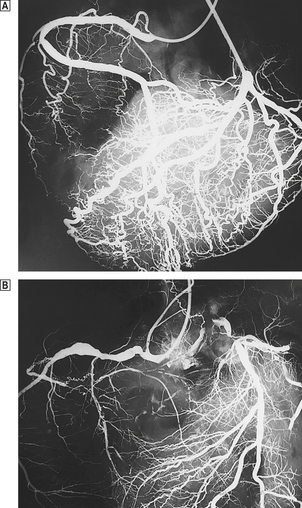

Capillary microangiopathy

This is the most important and characteristic change in diabetes. The alterations are found throughout the systemic circulation and can be viewed directly in the retina (Fig. 13.13). Small arterioles and capillaries are affected and the principal clinical effects are diabetic retinopathy, diabetic glomerulosclerosis and peripheral neuropathy. The biochemical changes are complex and include abnormal glycosylation of proteins within the vessel wall. Although thickened, the basement membranes are unusually permeable, and there is increased passive transudation of protein. Small vessels dilate, forming capillary micro-aneurysms. In the eye, protein leakage stimulates a fibrous and vascular response, which damages the complex neural network of the retina. Capillary thrombosis causes retinal ischaemia. This is a stimulus to the ingrowth of new capillaries, which causes further retinal damage. Some degree of diabetic retinal disease is inevitable in longstanding diabetes, but only a minority of patients become blind. Intimal thickening of renal arterioles and micro-aneurysm formation in the glomerular capillaries are the underlying causes of diabetic renal disease. The excretion of small amounts of protein in the urine (micro-albuminuria) is the first evidence of this. Peripheral neuropathy results from disease of small vessels supplying nerves. Multicentre trials have shown that the rate of progression of major complications such as diabetic retinopathy and nephropathy can be reduced by careful control of blood sugar levels and prompt treatment of hypertension.

image

Fig. 13.13 Fluorescein angiogram of the eye of a diabetic patient. Note the numerous, small, dot-like capillary micro-aneurysms.